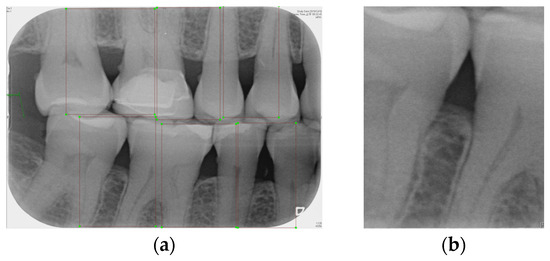

2.2. Image Segmentaion

BW images are particularly effective in capturing the alveolar crest. According to the literature [26], BW images maintain an orthogonal projection between the bone and teeth, reducing image distortion caused by improper shooting angles compared to periapical radiographs. In contrast, due to their curved projection, dental panoramic radiographs suffer from distortion and limit the observation of subtle changes in bone structure [27]. Therefore, this study utilizes the detailed view of gingival and dental structures provided by vertical BW images to assess the severity of intrabony defects. Since it is necessary to image the teeth and gingival symptoms to classify the degree of periodontal erosion using CNN, this study requires processing the image of a single gingival symptoms for CNN analysis. In this study, the YOLOv8 model will be trained, and the built-in segmentation function will be used to achieve a single gingival image.

2.2.1. Annotation of Tooth

Labeling was used as a tool, and by utilizing the rectangular tool, the marking range was from a single tooth section to another tooth section, which helps to accurately mark the actual condition of the gingiva around the middle of the tooth. Finally, the image was saved as a YOLO file and labeled as shown in Figure 2a. This process highlights the target area in the image and provides clearer information for CNN training.

Figure 2. Image annotation and segmentation. (a) Image Annotation Diagram. (b) The tooth segmentation result.